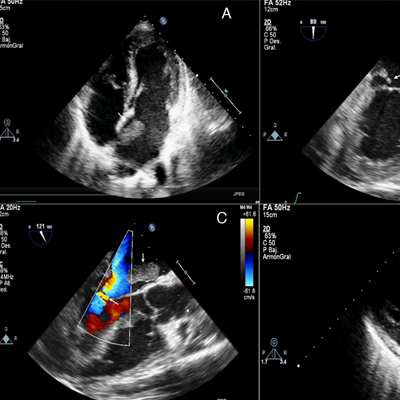

Ecocardiograma

El ecocardiograma es un estudio que utiliza el ultrasonido para crear imágenes del corazón, que permiten conocer su estructura y funcionamiento.

Ecocardiograma de estrés

Es un estudio de ecocardiograma en el que se aumenta los requerimientos del corazón mediante ejercicio o fármacos y permite identificar enfermedad de las arterias coronarias.

Ecocardiograma transesofágico

Procedimiento que utiliza el ultrasonido para producir imágenes del corazón en tiempo real en múltiples posiciones desde el esófago.